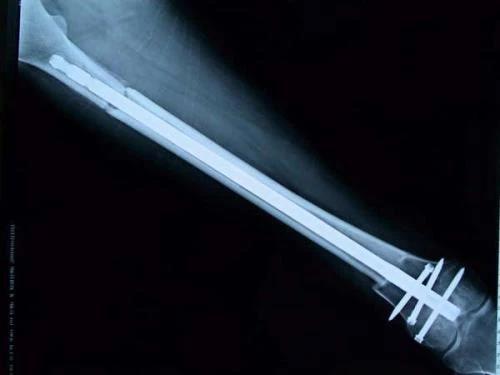

新輔助化療的目的是盡早殺滅遠(yuǎn)處微小轉(zhuǎn)移灶,縮小腫瘤及周圍炎性水腫反應(yīng)區(qū),以利于后續(xù)的保肢手術(shù);觀察腫瘤對化療的敏感性,為進(jìn)一步指定個體化的術(shù)后化療方案奠定基礎(chǔ)。骨肉瘤新輔助化療下的保肢治療如下圖所示:

新輔助化療藥物使用原則為:序貫用藥或聯(lián)合用藥,每個患者至少要選用兩種以上藥物,根據(jù)藥物說明書,靜脈或動脈給藥。初次用藥按照標(biāo)準(zhǔn)方案的藥物劑量計算給藥劑量。盡量維持總的藥物劑量強(qiáng)度。在嚴(yán)密觀察化療效果的前提下,建議至少用藥2個周期;根據(jù)所選用的標(biāo)準(zhǔn)方案要求間隔用藥。